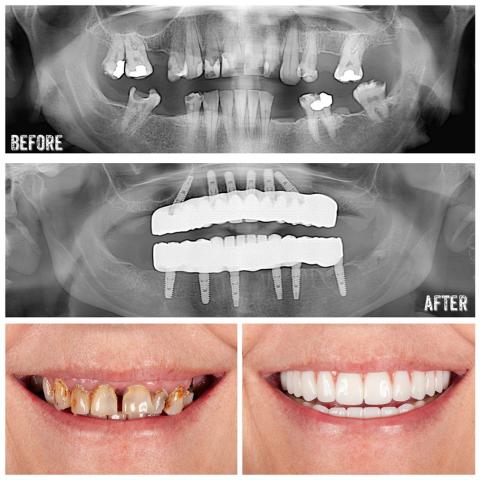

Dental Treatments